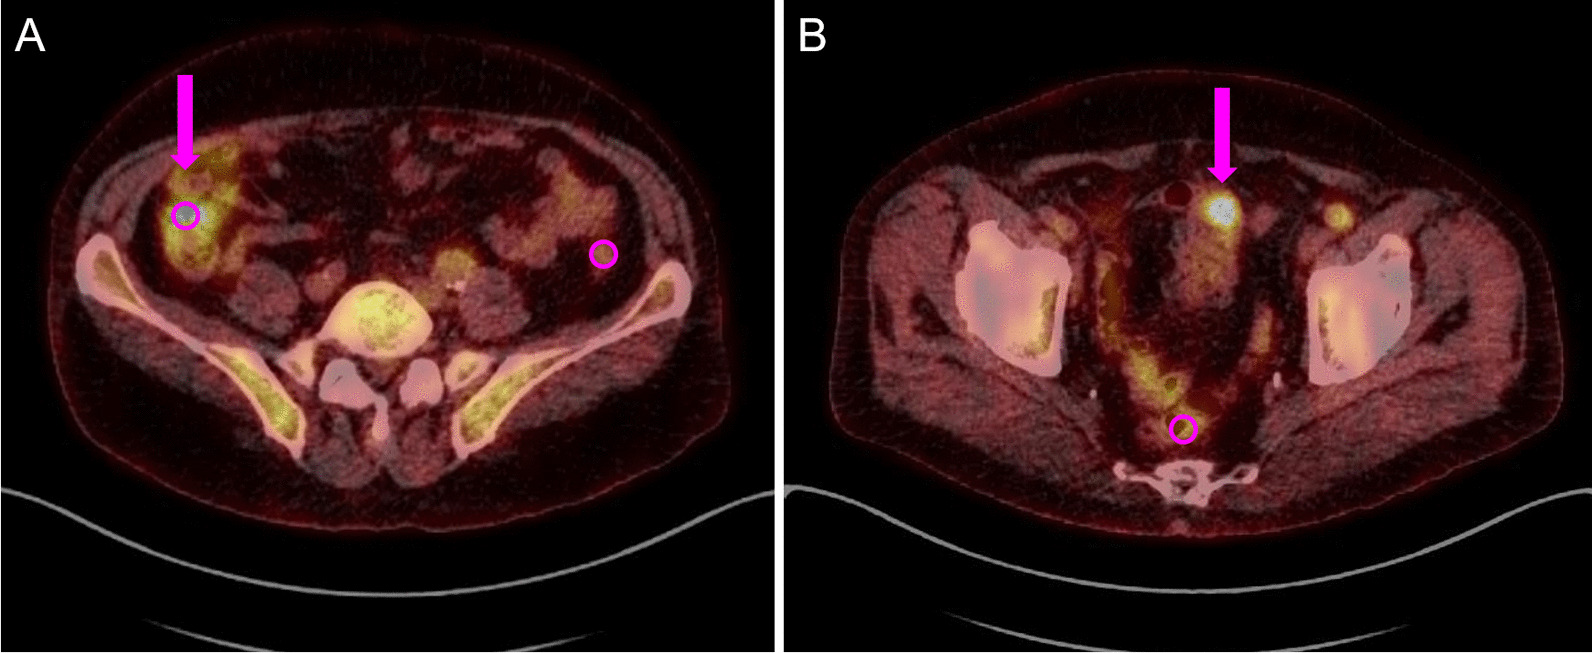

Fig. 1.

Exemplary depiction of FDG uptake in the bowel of two patients, representing quantitative and subjective assessment. A Uptake in the ascending colon (arrow); intensity: moderate, focality: diffuse, probability of being pathologic: probable physiologic, theoretical endoscopy recommendation: no. B Uptake in the sigmoid colon (arrow); intensity: high, focality: focal, probability of being pathologic: probable pathologic, theoretical endoscopy recommendation: yes. Standard sized spherical measurement regions (VOI) of SUVmean shown as circles with a diameter of 1.0 cm in ascending colon, descending colon (both A) and rectum (B)